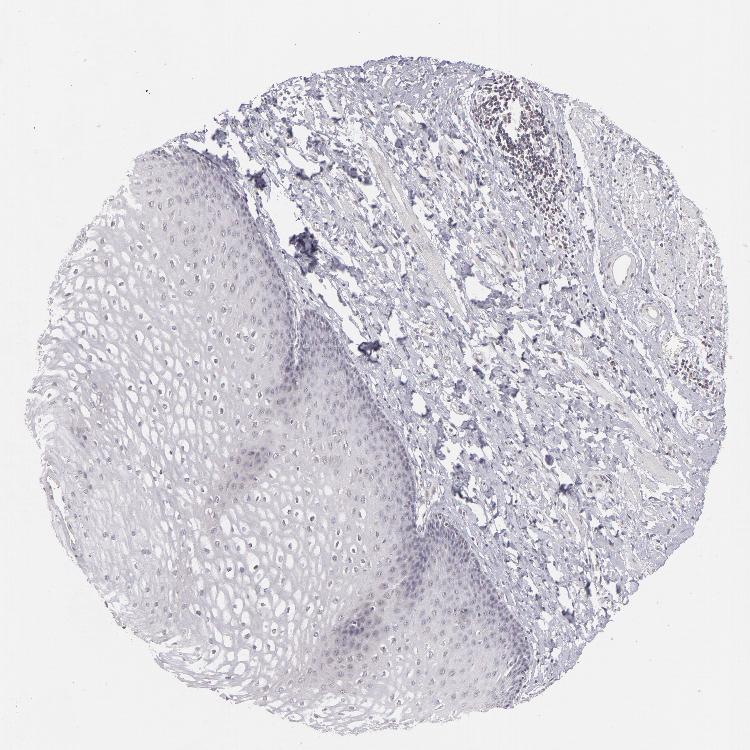

ESOPHAGUS - Antibody stainingi

Antibody staining in the annotated cell types in the current human tissue is reported as not detected, low, medium, or high, based on conventional immunohistochemistry profiling in selected tissues. This score is based on the combination of the staining intensity and fraction of stained cells.

Each image is clickable and will lead to virtual microscopy that enables deeper exploration of all samples and also displays staining intensity scores, fraction scores and subcellular localization as well as patient and tissue information for each sample.

Antibody HPA001586

Squamous epithelial cells Not detected